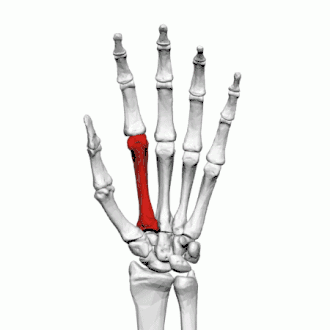

Deuxième métacarpien

Description

Le deuxième métacarpien est le plus long des métacarpiens.

Base

Sa base est prolongée vers le haut et vers le milieu une crête proéminente. En arrière et en dedans se présente un processus styloïde.

Sa face supérieure présente trois facettes articulaires de dehors en dedans pour : le trapèze, le trapézoïde et le capitatum.

Médialement, il présente une facette pour le troisième métacarpien.

Au niveau du processus styloïde s'insère le muscle long extenseur radial du carpe.

Sa face palmaire donne insertion au muscle fléchisseur radial du carpe.

Corps

La diaphyse donne naissance au premier muscle interosseux palmaire et aux premier et deuxième muscle interosseux dorsaux de la main.